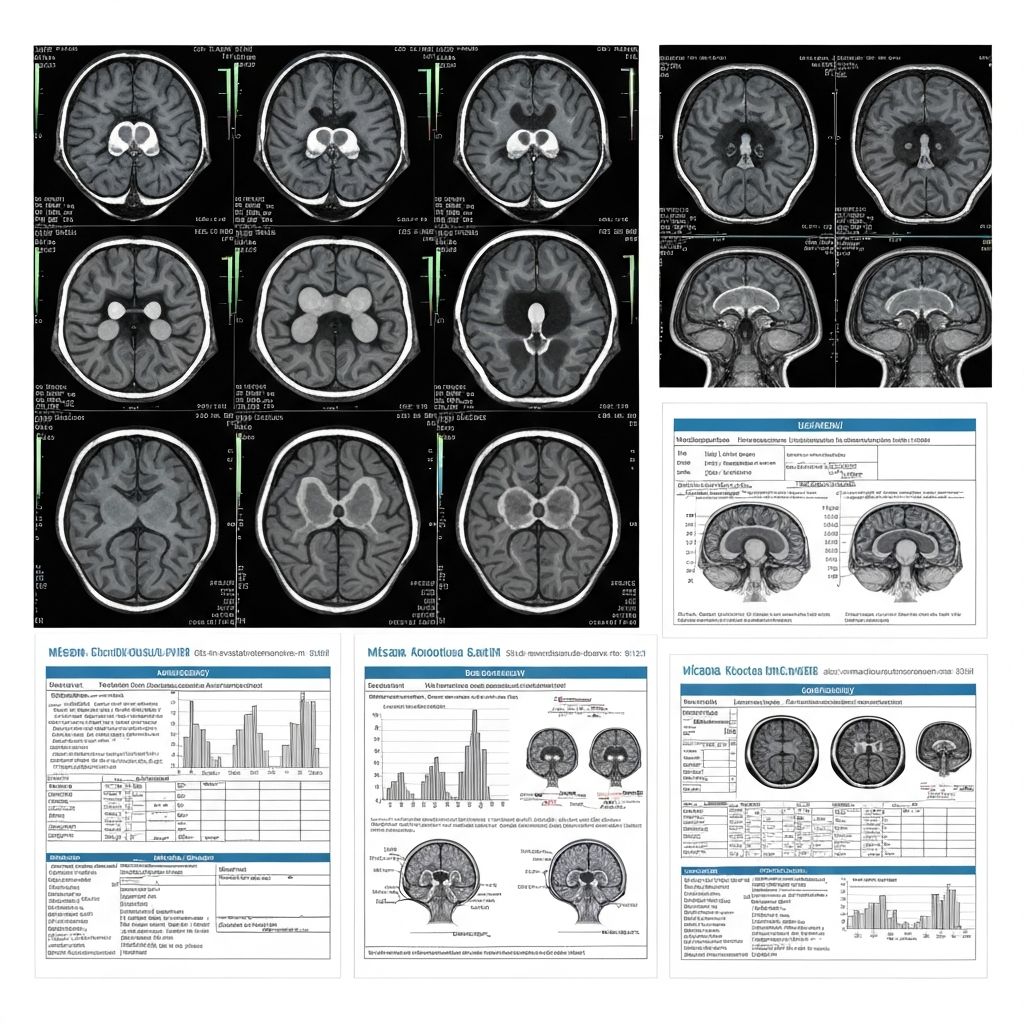

Dive deep into the fascinating world of neurology, studying the brain, spinal cord, and nervous system. Learn about neurological disorders, diagnostic techniques, and cutting-edge treatments from experienced neurologists.

Interactive sessions on neuroanatomy, disorders, and diagnostic approaches

Neurology medical case project with mentor and presentation preparation